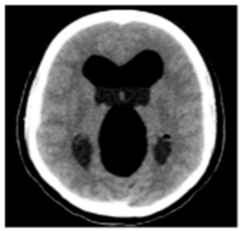

| Original Medical Images | |||||||

| Pair 1 | Pair 2 | Pair 3 | Pair 4 | ||||

![]() (1-9) PSNR = 44.14 | ![]() (1-10) PSNR = 41.90 | ![]() (1-11) PSNR = 40.09 | ![]() (1-12) PSNR = 41.41 | ![]() (1-13) PSNR = 42.24 | ![]() (1-14) PSNR = 40.35 | ![]() (1-15) PSNR = 40.79 | ![]() (1-16) PSNR = 40.84 |

| Shadow Images Produced by Using LSBs | |||||||

![]() (1-17) PSNR = 26.35 | ![]() (1-18) PSNR = 25.49 | ![]() (1-19) PSNR = 23.57 | ![]() (1-20) PSNR = 24.19 | ![]() (1-21) PSNR = 24.79 | ![]() (1-22) PSNR = 24.23 | ![]() (1-23) PSNR = 23.26 | ![]() (1-24) PSNR = 24.42 |

| Shadow Images Produced by Using Middle Bits | |||||||

![]() (1-25) PSNR = 18.97 | ![]() (1-26) PSNR = 19.95 | ![]() (1-27) PSNR = 14.10 | ![]() (1-28) PSNR = 13.84 | ![]() (1-29) PSNR = 16.66 | ![]() (1-30) PSNR = 13.23 | ![]() (1-31) PSNR = 13.38 | ![]() (1-32) PSNR = 14.75 |

| Shadow Images Produced by Using MSBs | |||||||